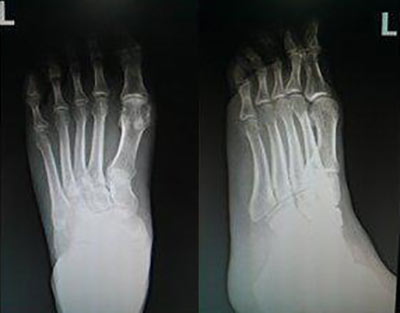

查体:左踝关节疼痛不适,左足第一跖趾可见痛风石形成,且红肿、触痛。

实验室检查:C反应蛋白391mg/L,血沉69mm/H,尿酸428.6umol/L,葡萄糖3.5 mmol/L,肌酐125 umol/L。

临床诊断:痛风经过检查结果并结合邓先生个人体质,我院章晓辉主任为他采用个性化治疗方案并辅以相应的辅助治疗,以达到恢复体内嘌呤代谢正常,血尿酸平衡,实现标本兼治的目的。

治疗第三个疗程结束后,邓先生的左踝关节已恢复正常,关节转动灵活,左足第一跖趾关节红肿完全消退,无压痛,痛风石全部溶解。为了加强疗效,章晓辉主任又为邓先生进行了辅助治疗,从根本上解决痛风反复复发的情况。

三个月后,邓先生来院复查,章晓辉主任为其进行了系统检查,数据显示各项指标均一切正常,尿酸降至正常范围,痛风症状全部消除,恢复正常健康状态。